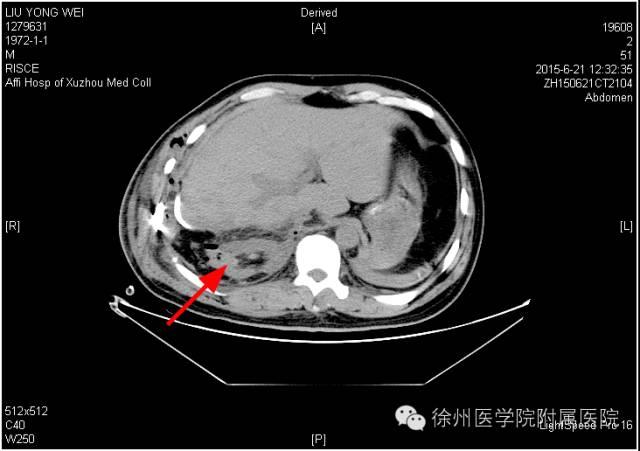

该声明称,患者手术时间是2015年6月20日,术后分别于2015年6月21日(术后第1天)和6月25日(术后第5天)的2次CT复查均显示该患者的右肾存在。

该声明还专门张贴了两张CT复查图。

图一 2015年6月21日(术后第1天)CT,右肾如箭头所示。